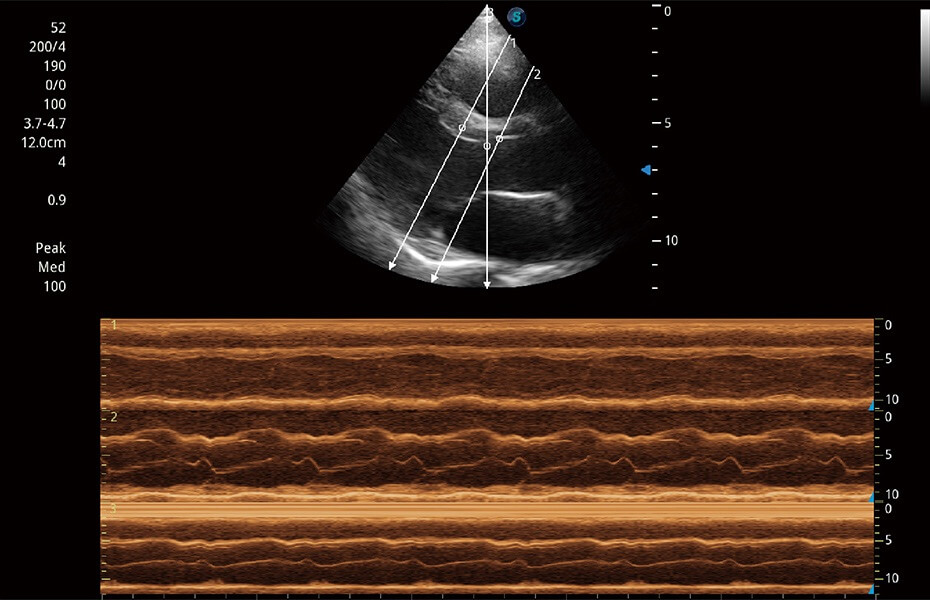

ProPet 60 作為一款高端臺式動物超聲設(shè)備,為動物醫(yī)生的日常診斷提供了一系列貼合動物臨床需求、解決臨床實際問題的高級成像功能。憑借全系列高清探頭,滿足醫(yī)生對腹部、心臟、生殖、淺表、肌骨等成像的所有需求,切實幫助您提升檢查效率,提高診斷信心。